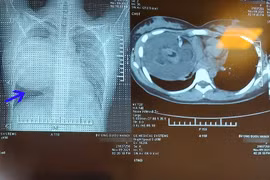

Các bác sĩ bệnh viện Ung bướu Hà Nội vừa phẫu thuật lấy khối u quái khổng lồ trong lồng ngực cô gái 19 tuổi. Khối u to, đè đẩy tim, chèn ép làm xẹp phổi, dính nhiều cơ quan nội tạng xung quanh.